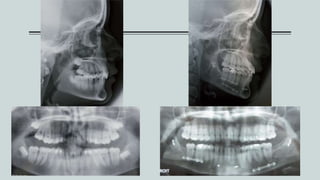

Panoramic x-ray revealed that the condyles and mandibular ramus were

asymmetrical absence of radicular parallelism, mild loss of the alveolar

crests and a crown-root ratio of 1:2

Cephalometric data revealed a skeletal class I

with a soft dolichofacial growth direction,

upper incisor protrusion and normally inclined

incisors